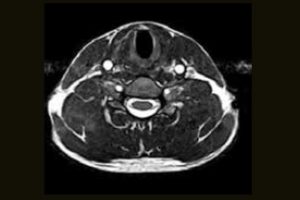

Clinical Images

Immediate access to high quality MR images can help your practice achieve new levels of efficiency and patient satisfaction. From C-spine anomalies to foot injuries, the S-scan dedicated MRI system efficiently delivers a range of MSK MRI studies within your existing practice.

Comprehensive MSK Imaging